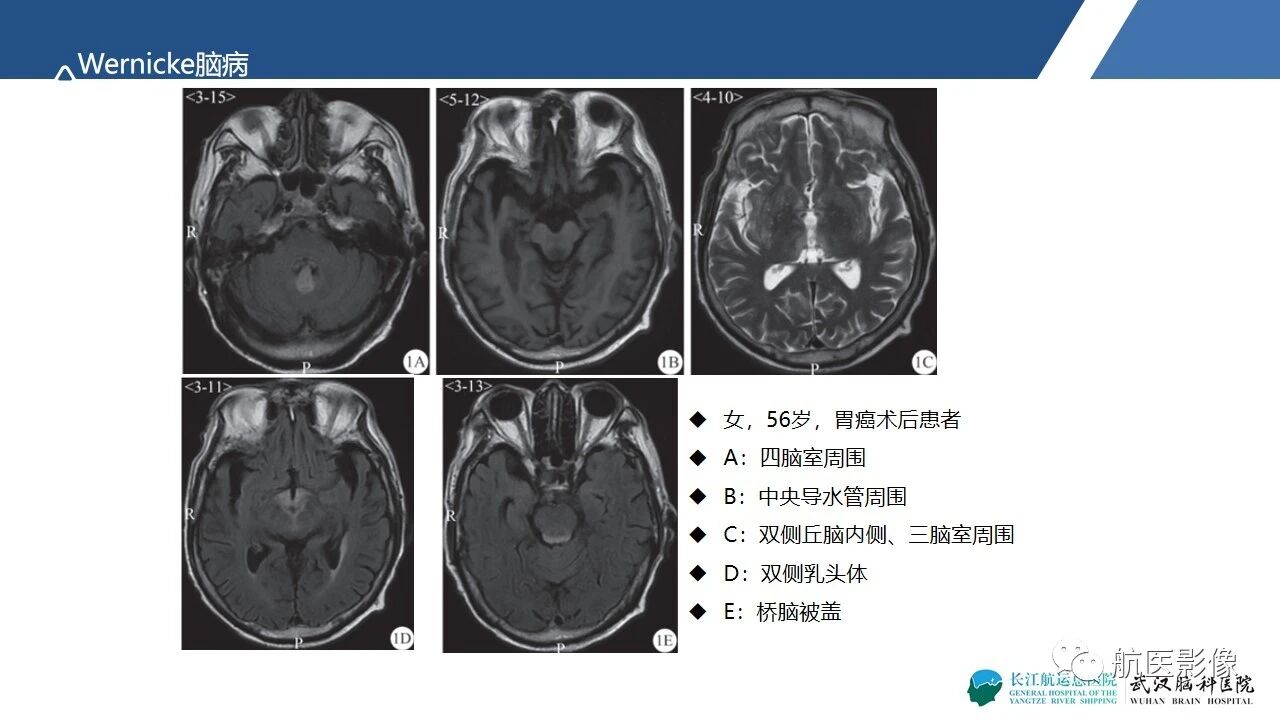

基底节区、丘脑对称性病变影像表现